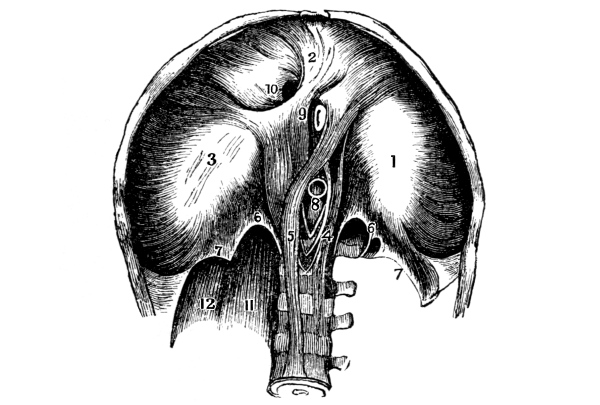

The Heart, 101—The Pericardium, 101—Cavities of the Heart, 103—The Endocardium, 103—The Valves of the Heart, 103—Circulation, 105—Circulation in the Fetus, 106—Arteries, 107—Veins, 109—Portal Circulation, 109—Pulmonary Circulation, 110—Nerves of the Heart, 110—Heart Sounds, 111—The Heart Beat, 111—Factors Affecting Circulation, 112—The Pulse, 113—Blood Pressure, 114—Nerve Supply of the Blood-vessels, 115—The Blood, 116—Composition of the Blood, 116—Coagulability of the Blood, 117—Blood-corpuscles, 118. |